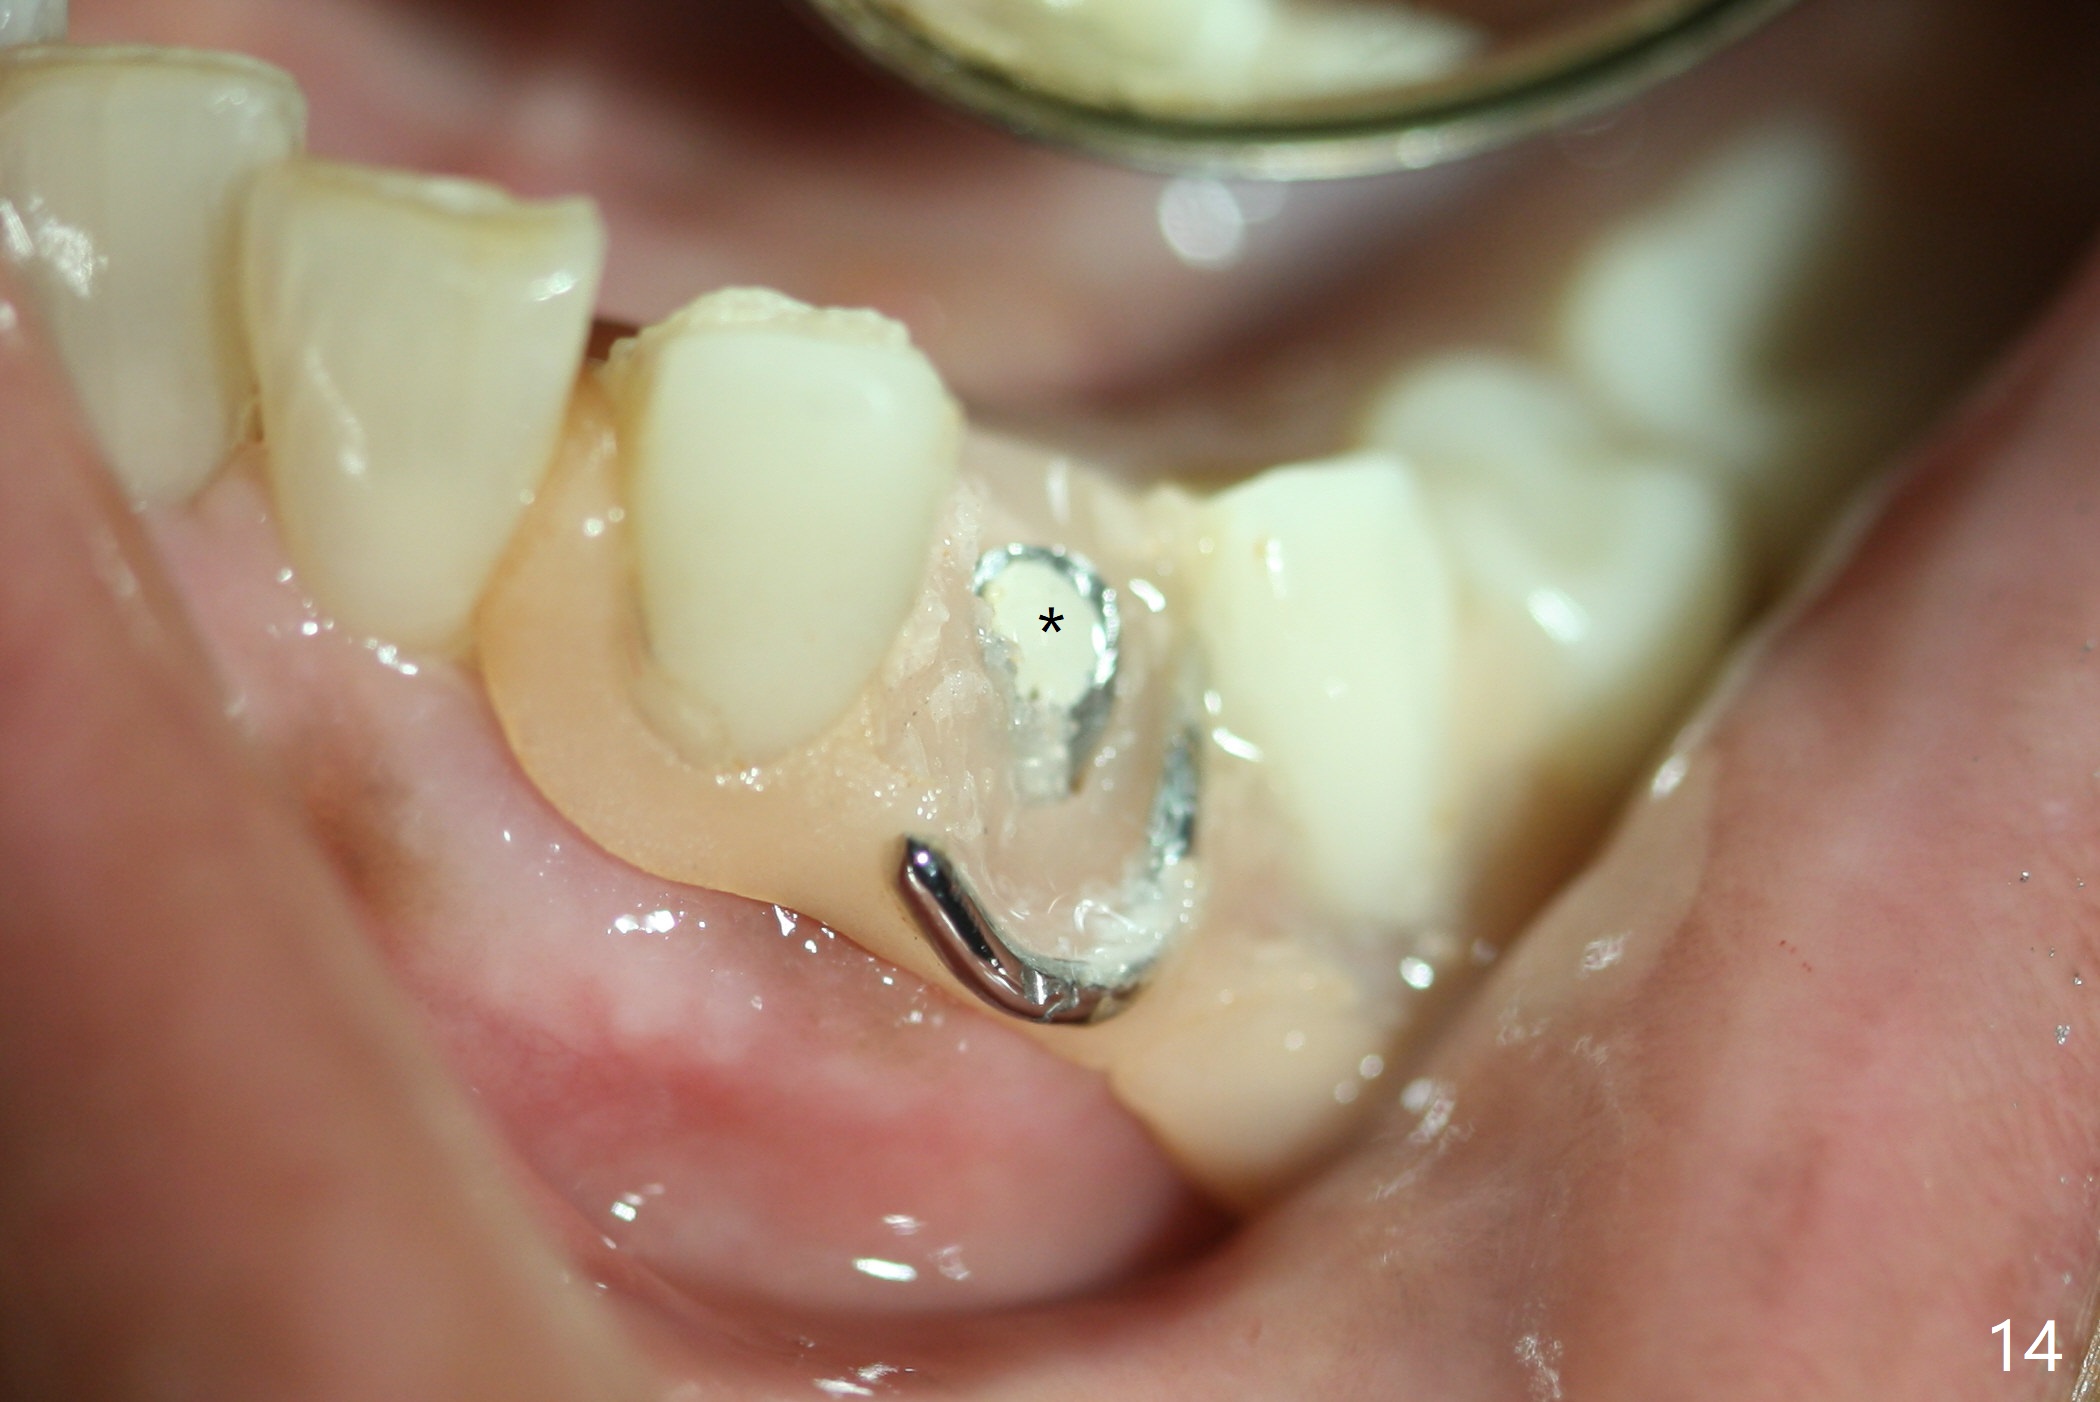

The inflammation around the tooth #22 (Fig.1 *) and mobility may be related to trauma from the only clasp of the lower flipper (Fig.2). The latter is loose with space underneath (>) and laterally (Fig.3 *). The distobuccal plate is defective upon extraction; the osteotomy is initiated in the mesiolingual slope of the socket (Fig.4) with ~ 6 mm native bone. When a 3.8x15 mm dummy implant achieves insertion torque of 50 Ncm, the insertion is incomplete with apical space (Fig.5 *). The definitive implant (3.8x13 mm) closes the apical space and obtains insertion torque >55 Ncm; a ball abutment with 2 mm cuff seems to be short for retention (Fig.6). A 4.5x4(5) mm cemented abutment (Fig.7,8) seems appropriate for retention after soft reline of the lower flipper (Fig.9-11). The socket heals without bone graft exposure 8 days postop (Fig.12,13). To satisfy the patient's desire to have a white tooth, the buccal portion of the soft reline and the abutment is removed (Fig.14) and a crown form is added (Fig.15 *). The socket obliterates 3 months postop (Fig.16).